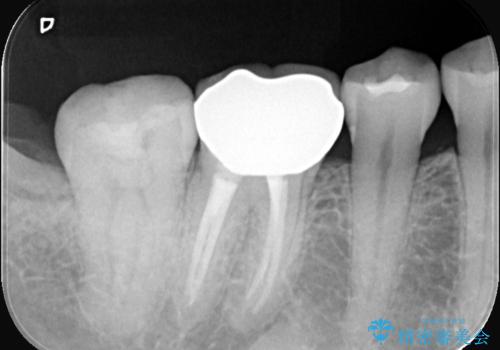

クリーニングにいらした患者さんで、右下7番目の歯の奥側の面や手前の歯との間にう蝕があり、噛む面にも蝕処置によるレジン材料が詰まっていたことから、う蝕も古い材料も全て除去しセラミックインレーでのやり替えとなりました。

右下7近遠心にカリエスを認め、咬合面のCR修復も劣化していたので、カリエスと古い材料を全て除去し新しくCR裏層した後、セラミックインレーをセットしています。セット時はラバーダム防湿を行っています。